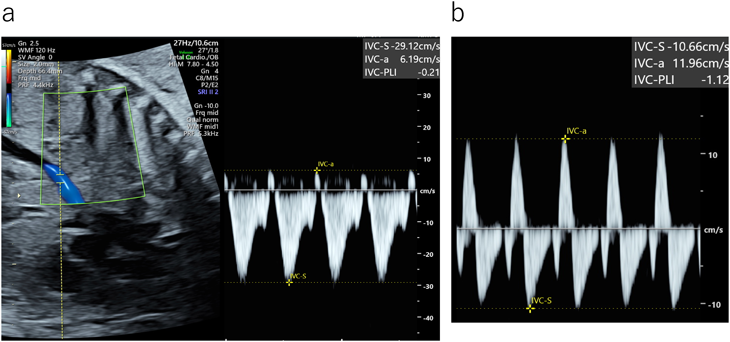

・下大静脈・臍帯静脈

下大静脈(右心房への流入部)では,心房収縮期の血流(A波)は逆流波となる.心房収縮期の逆流速度と心室収縮期の流入速度の比であるPreload Index(PLI)が用いられる(Fig. 8).0.5以上は異常と考える25, 26).一方,臍帯静脈は正常では定常流であるが(Fig. 9a),静脈圧の上昇に伴いpulsation(波動)を認めるようになる(Fig. 9b).Pulsationの周期は心周期と一致しており心房収縮期に谷となる9).胎児の呼吸様運動でもpulsation様に描出されるが,心周期と一致せずに周期が長いことから区別される(Fig. 9c). PLI 心房収縮期の逆流速度A 心室収縮期の流入速度S

Pediatric Cardiology and Cardiac Surgery 40(4): 250-259 (2024)

Fig. 8 下大静脈血流波形

a:正常 矢状断にて右心房への流入部付近で計測.下大静脈では正常でも心房収縮により逆流波となる.Preload index (PLI)=6.19/29.12=0.21.b:心房収縮により逆流波が増高しPLIは顕著に上昇している.PLI=11.96/10.66=1.12.